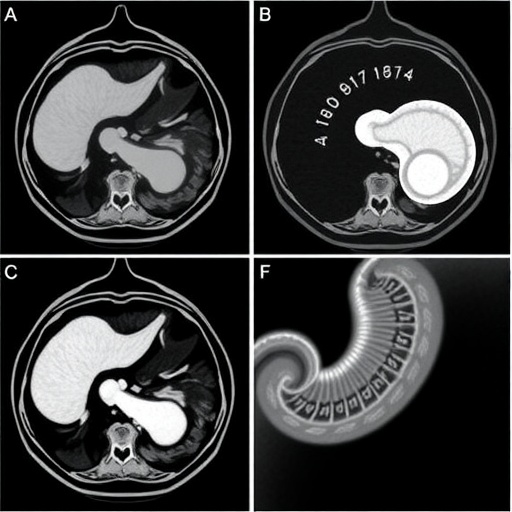

In a groundbreaking study set to reshape the understanding of inflammatory bowel disease (IBD) in pediatric patients, researchers have identified significant hepatobiliary and pancreatic findings through magnetic resonance enterography (MRE). This imaging technology has emerged as a critical tool in the diagnosis and management of inflammatory bowel conditions, enhancing the accuracy and depth of the assessments available to clinicians. The research, led by an experienced team, including L. Scheller, J. Dillman, and K. Epstein, offers novel insights into the complex interplay between gastrointestinal and hepatobiliary health in children afflicted with IBD.

The significance of this study cannot be overstated, as it elucidates the often-overlooked aspects of hepatobiliary and pancreatic pathologies concomitant with inflammatory bowel disease. MRE has gained traction as a non-invasive modality, providing vivid images that can pinpoint abnormalities, differentiate between various forms of IBD, and showcase organ involvement. In the context of pediatric patients, these findings are particularly crucial, considering the long-term implications of uncontrolled inflammation that can lead to substantial morbidity.

The preliminary outcomes of this research reveal an intriguing association between the severity of IBD and the presence of changes in the hepatobiliary system. Through the comprehensive examination of MRE images, it appears that children with newly diagnosed IBD frequently exhibit alterations in their liver and pancreatic structures, which can serve as a precursor to potential complications if not managed appropriately. This raises essential questions about routine imaging practices and the necessity for an interdisciplinary approach involving pediatric gastroenterologists and radiologists.

In summary, the combination of advanced imaging techniques like magnetic resonance enterography and a detailed examination of hepatobiliary and pancreatic findings in children newly diagnosed with inflammatory bowel disease marks a pivotal moment in pediatric gastroenterology. The implications of this research are bound to affect clinical practices, inform treatment paradigms, and above all, elevate the standard of care for vulnerable populations facing chronic and relapsing conditions. As more pediatric patients are diagnosed with IBD, the importance of integrating comprehensive imaging approaches is clearer than ever.

Article Title: Hepatobiliary and pancreatic findings on magnetic resonance enterography examinations in children with newly diagnosed inflammatory bowel disease.